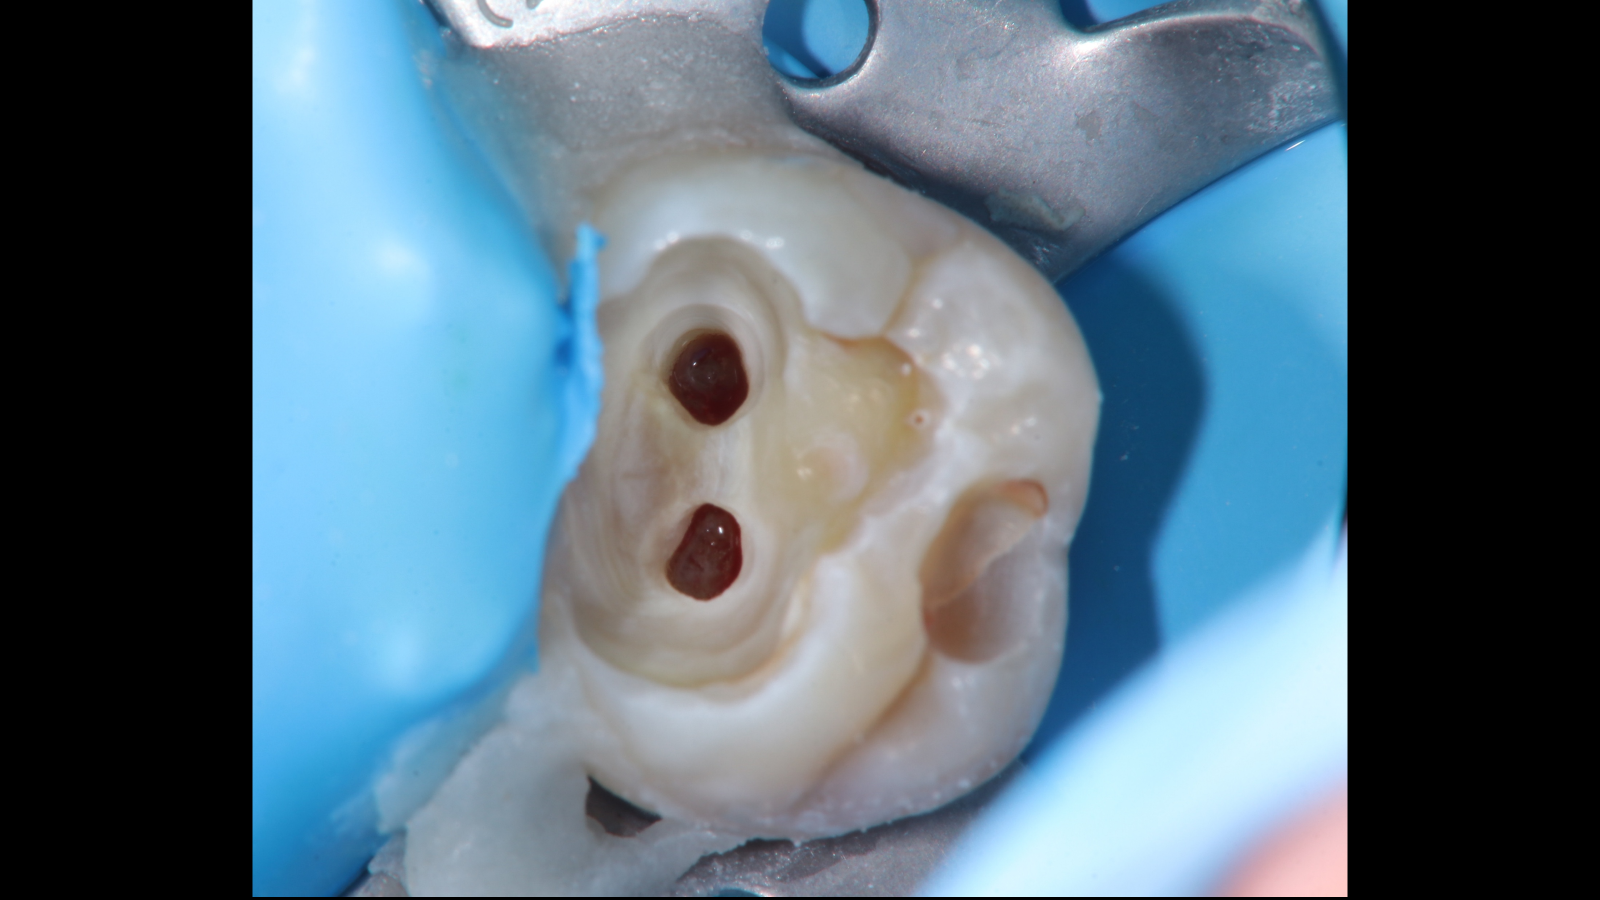

ラバーダム防湿下にてう蝕除去を行ったところ、歯髄の露出を認めました。

露出歯髄は鮮紅色で出血のコントロールが可能であり、不可逆性歯髄炎を示唆する所見は認められなかったため、歯髄温存が可能と判断しました。

露出部の歯髄に対して部分断髄を行い、止血確認後にMTAセメントを用いた歯髄保護処置を行いました。